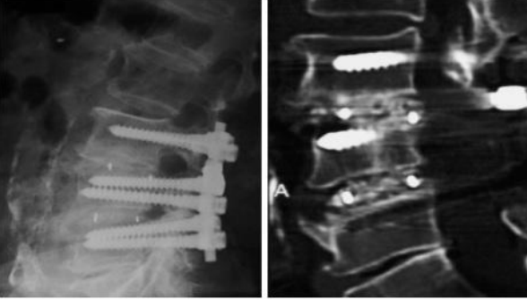

2.椎间远期融合效果好,沉降率低

注册证名称:医用纳米羟基磷灰石/聚酰胺66复合骨充填材料

1.良好的生物活性、结合植骨增强骨融合